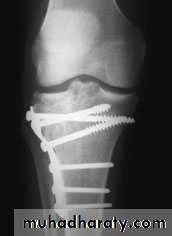

Undisplaced fractures treated conservatively: Haemarthrosis aspiration and compression bandaging,above knee cast for one months followed by functional brace and physiotherapy.For displaced fractures treatment is by open reduction and internal fixation with plate and screws as it is an intra articular fracture.

fixation of tibial plateau fracture